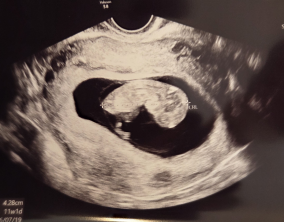

믿음 끝에 찾아온 첫 기적

심장소리 이후, 함께 웃게 된 임밍아웃